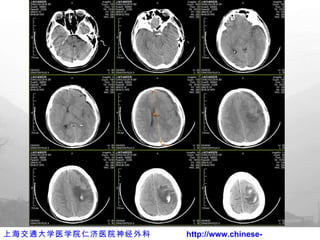

伤后  2h CT